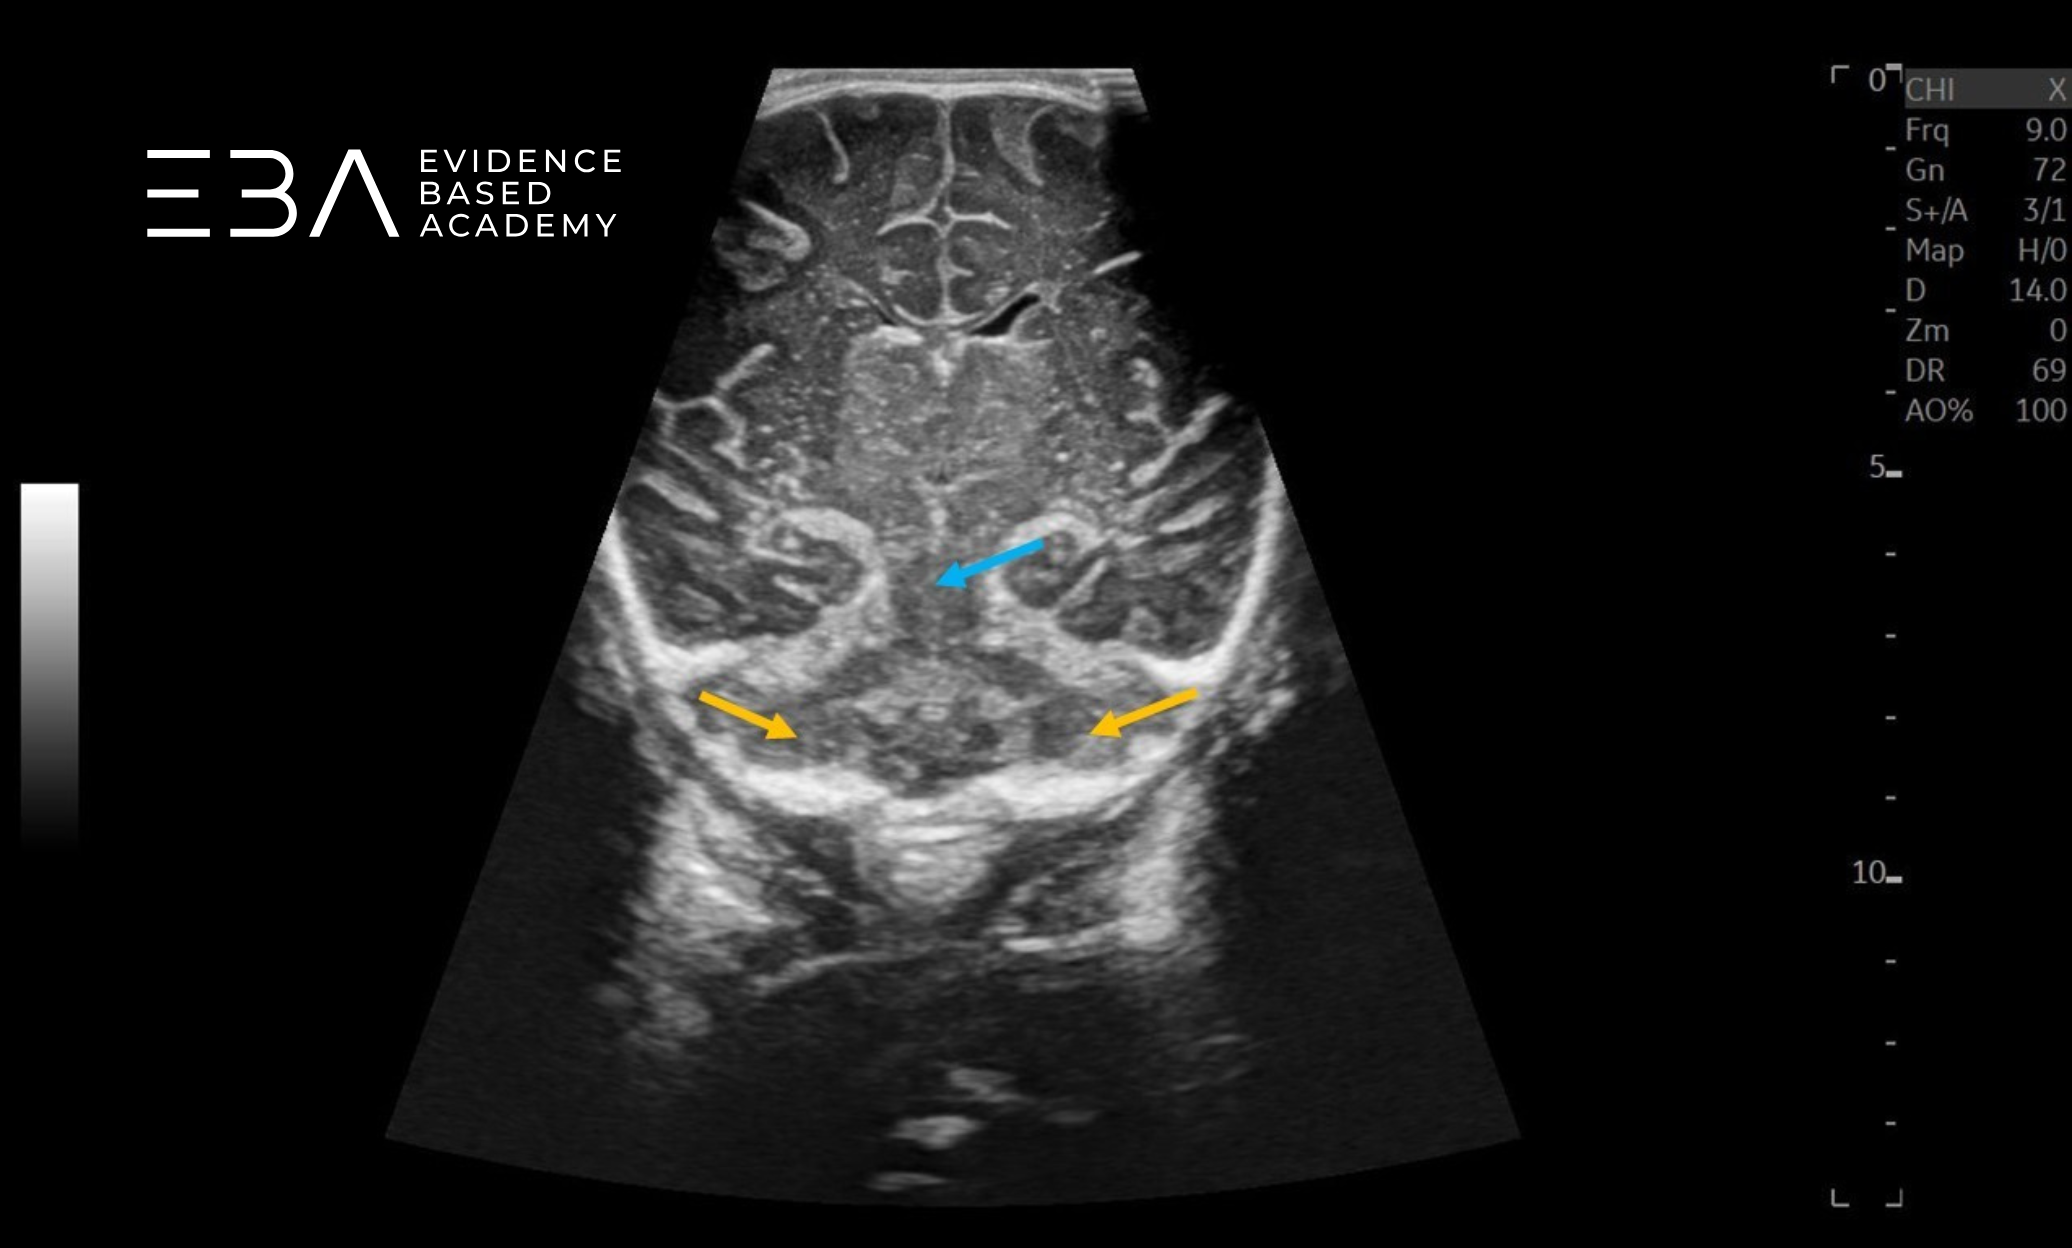

zdj. 1

Głowica mikrokonweksowa. Brak symetrii, wynikającej z nieco skośnego przyłożenia głowicy utrudnia ocenę. Strzałką zaznaczono prawy splot naczyniówkowy.